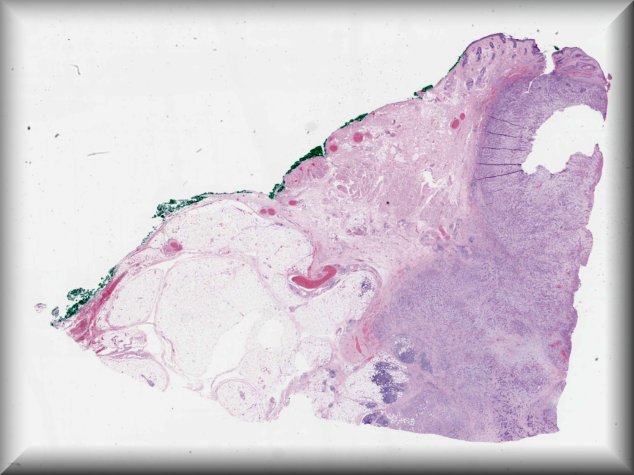

Luciane Dreher Irion (Manchester): 53-year-old male with a 6 month history of proptosis and right subconjunctival lump extending to temporal orbit. Incisional episcleral biopsy performed. |